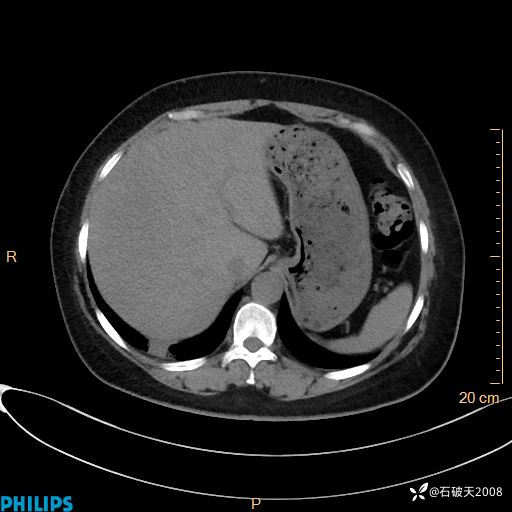

静脉期